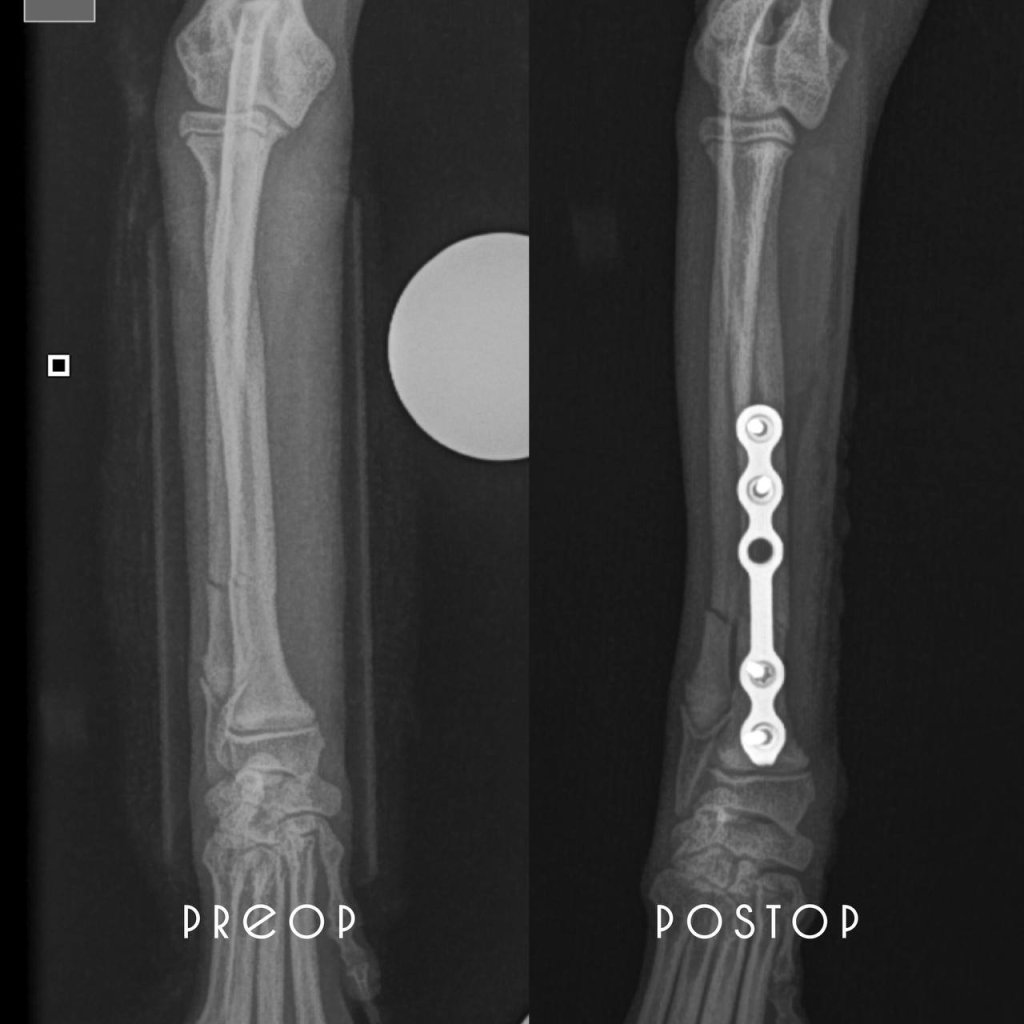

ОСТЕОСИНТЕЗ ПРИ ПЕРЕЛОМЕ КОСТЕЙ ПРЕДПЛЕЧЬЯ

Аффенпинчер

возраст 5 мес

масса тела 2 кг

P.S уважаемые владельцы, ни в коем случае не соглашайтесь на постановку лангеты при переломах 🙏 это ведёт за собой ряд осложнений (несращения/деформации/пролежни)